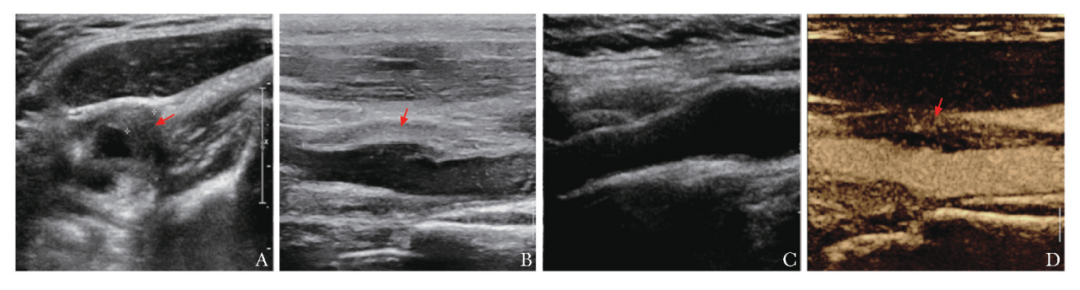

颈动脉超声查验发现左颈总动脉分叉处及左颈内动脉肇端段管壁周围局限性增厚低回声,与闲居管壁分界不清,厚约0.46cm(图2A),累计长度约3.0cm(图2B),合乎血管壁周围炎推崇,右颈动脉未见特殊(图2C);进一步行超声造影(CEUS)查验,左颈总动脉管壁周围增厚的低回声内可见迷漫的片状微泡造影剂散播,呈彰着增强,教导疾病处于行动期(图2D)。

图2患者初诊老例灰阶超声及超声造影查验限度

左颈总动脉分叉处及左颈内动脉肇端段管壁周围低回声,呈偏心地增厚,厚约0.46cm(A,箭头),累计长度约3.0cm(B,箭头),右颈动脉未见特殊(C),左颈总动脉管壁周围增厚的低回声内可见迷漫的片状造影剂微泡填充,呈彰着增强(D,箭头)